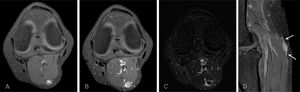

The acquisition of T1-weighted sequences prior to contrast administration enables the increase in SI following contrast administration to be assessed by comparing the two sequences. Nevertheless, interpretation can sometimes still be complex despite the pre-contrast acquisition, specifically in lesions that are hyperintense in T1. It is difficult to assess the increase of SI in lesions that have high SI in T1 before intravenous contrast administration. Applying subtraction to the two sequences eliminates the areas with no uptake, making it easier to identify the areas with uptake12 (Fig. 1). However, the subtraction technique is limited by the patient moving between the two sequences as this causes a spatial misalignment of pixels. Subtraction images are especially useful in MR angiography studies, which make it easier to visualise distal vessels in maximum intensity projections. Likewise, in lesions with a haemorrhagic component, subtraction can suppress it and differentiate between haemorrhagic areas and areas with contrast uptake.

Use of non-GBCA-enhanced sequence. A) T1-weighted transverse image with spectral fat suppression. A soft tissue lesion is seen in the posterior region of the knee, with a hyperintense centre. B) T1-weighted image with spectral fat suppression after GBCA administration. C) Synthetic image obtained by subtraction (B − A), identifying peripheral contrast uptake, without enhancement in the centre of the lesion. D) Sagittal T1-weighted image after GBCA administration. Linear contrast enhancement adjacent to the lesion (arrows). AP: schwannoma of the sural cutaneous nerve.

Morphological analysis on static 2D images acquired after contrast agent administration is a first step to more accurately delineating lesions. The morphology of the uptake can be homogeneous, heterogeneous, nodular or linear. Areas with no contrast uptake within the lesions represent necrotic areas. Increased SI in structures adjacent to focal lesions can be a helpful associated finding in narrowing the differential diagnosis, even if it is non-specific. For example, in the central nervous system (CNS), dural enhancement in an extra-axial location adjacent to a lesion with marked contrast uptake is virtually diagnostic of meningioma (Fig. 2). Likewise, the uptake of a nerve in contiguity with an intensely enhancing soft tissue tumour narrows the differential diagnosis to a lesion of neural origin, such as schwannoma (Fig. 1D). Linear uptake in the topography of the cerebral sulci in cancer patients with clinical onset in several cranial nerves is highly suspicious for leptomeningeal metastases (Fig. 3). The morphology and location of delayed contrast uptake in cardiac MRI studies is critical. Subendocardial enhancements in defined coronary territories reflect the presence of fibrosis in chronic infarction. Mesoventricular or epicardial uptake enables the diagnosis of other entities such as hypertrophic cardiomyopathy, myocarditis or sarcoidosis.14